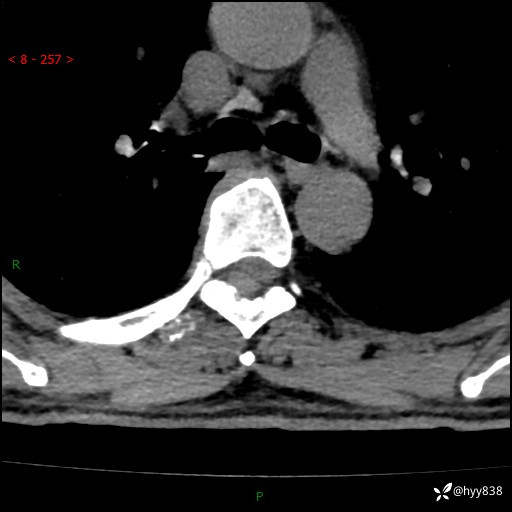

胸椎CT平扫(骨窗+软组织窗)